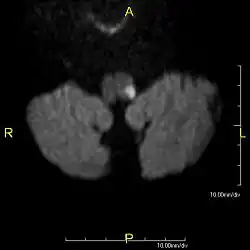

![]() | |

| Medulla oblongata, shown by a transverse section passing through the middle of the olive. (Lateral medullary syndrome can affect structures in upper left: #9=vagus nerve, #10=acoustic nucleus, #12=nucleus gracilis, #13=nucleus cuneatus, #14=head of posterior column and lower sensory root of trigeminal nerve and #19=Ligula.) | |